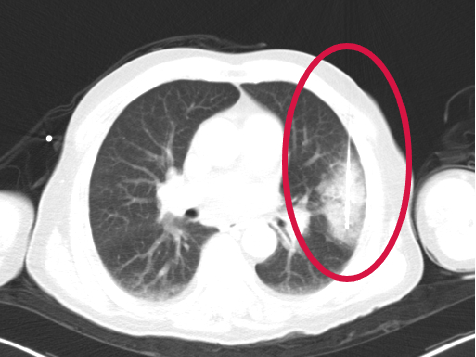

術(shù)前圖像

▲患者因體檢發(fā)現(xiàn)左肺上葉舌段結(jié)節(jié),考慮周圍型肺癌可能。因高齡、肺氣腫無法手術(shù),遂來院接受肺結(jié)節(jié)冷凍消融治療,術(shù)后病理為肺癌,定期隨訪提示腫瘤逐漸縮小。